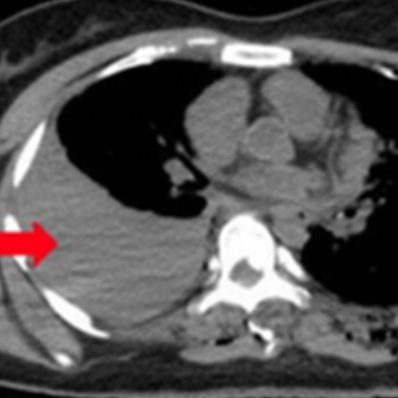

外傷性気胸

外傷性血胸